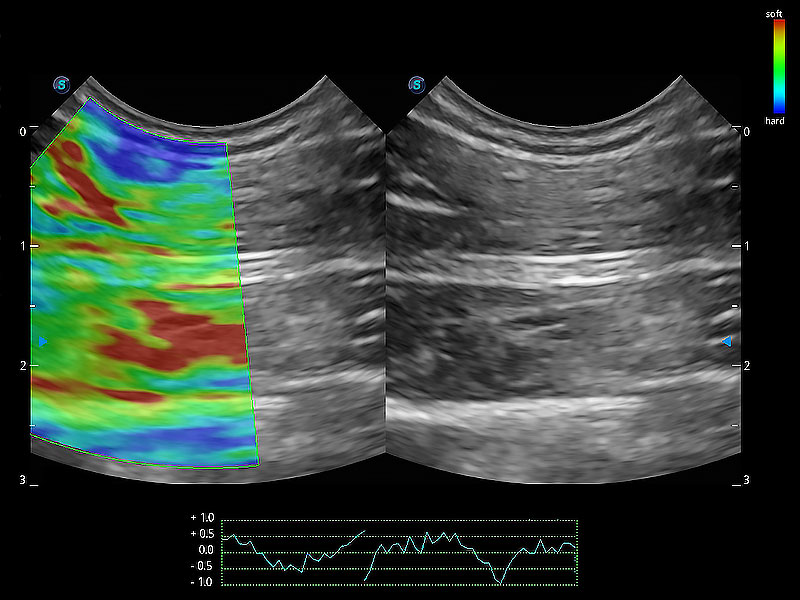

(犬)四腔心MQA

• MQA 心肌定量分析

通过心肌识别技术与二维斑点追踪技术相结合,对心脏的超声图像进行量化分析。计算心肌17个节段的应变、应变率、速度、位移等,并通过牛眼图的形式进行呈现。